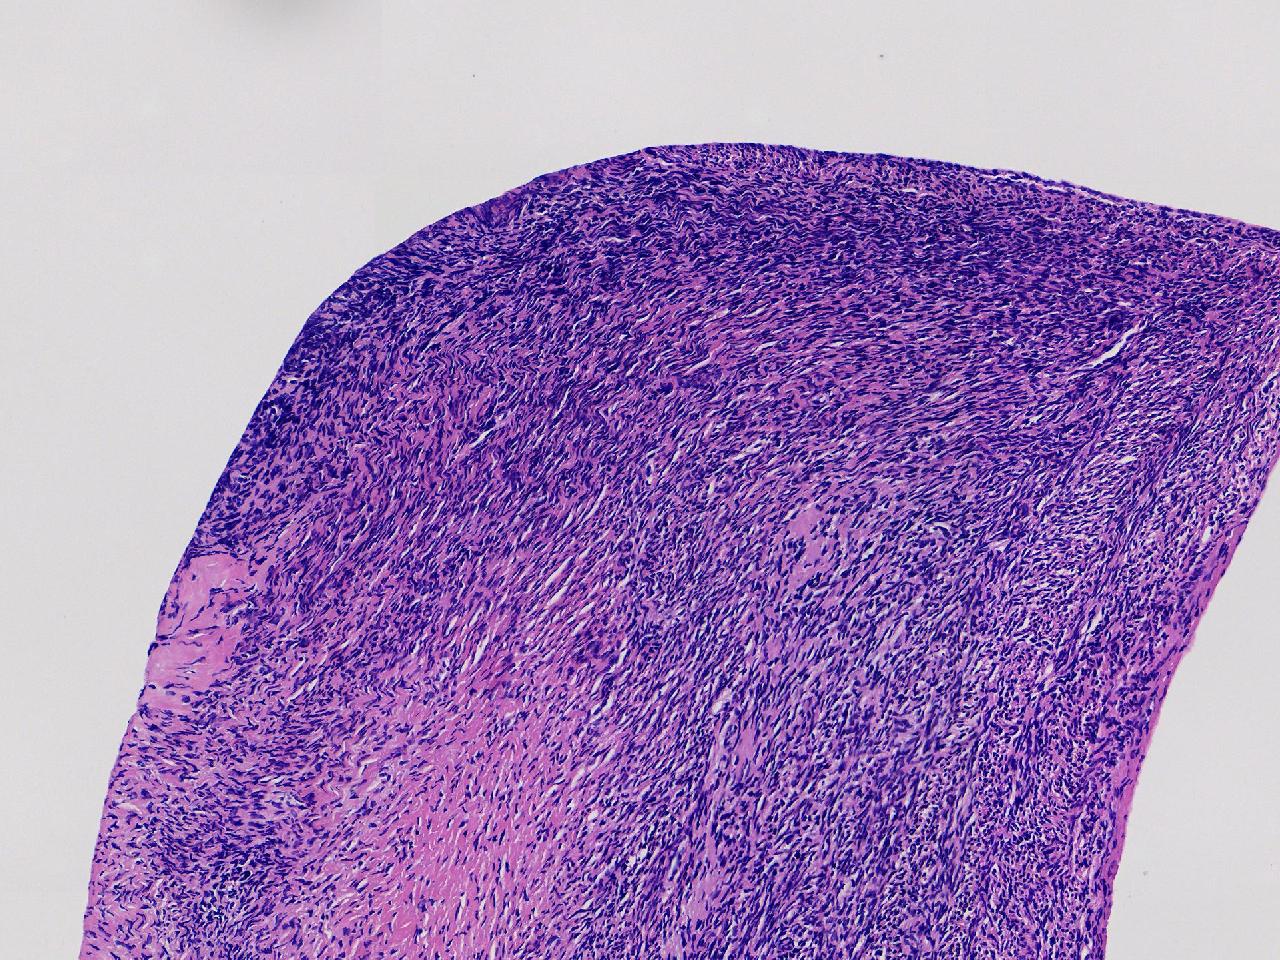

卵巢颗粒状突起活检。

女,34岁。右侧输卵管 异位妊娠,宫腔镜下见左侧卵巢颗粒状突起,取活检1块。

左侧卵巢颗粒状突起活检

灰白色不整形软组织1块,至今0.2厘米。

妊娠黄体瘤? 卵巢间质增生?

未见妊娠黄体瘤改变,见卵巢间质纤维增生。

卵巢间质纤维增生